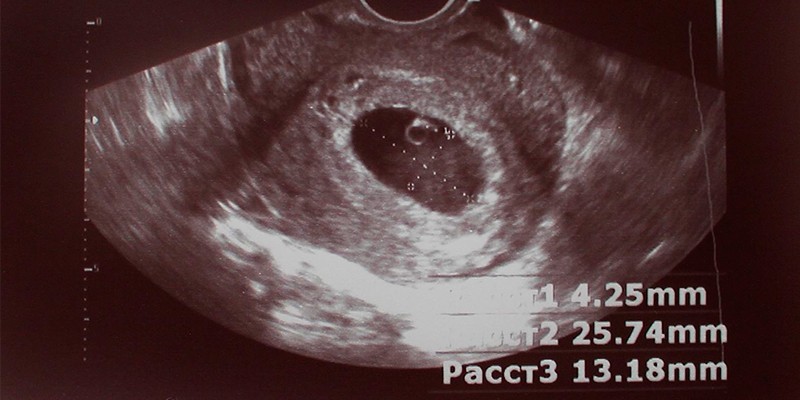

Толщина воротникового пространства

Размер шейной складки является продолговатым образованием, где скапливается жидкость. К 16-ой неделе на УЗИ его уже не увидят, поскольку оно исчезнет, а в I триместре толщина воротникового пространства (ТВП) растет. По этому показателю можно судить о наличии у ребенка генетических (хромосомных) отклонений, поэтому важно, чтобы он находится в пределах нормы:

|

Срок (недели) |

ТВП (мм) |

|---|---|

10 |

1,5–2,2 |

11 |

1,6–2,4 |

12 |

1,6–2,5 |

13 |

1,7–2,7 |